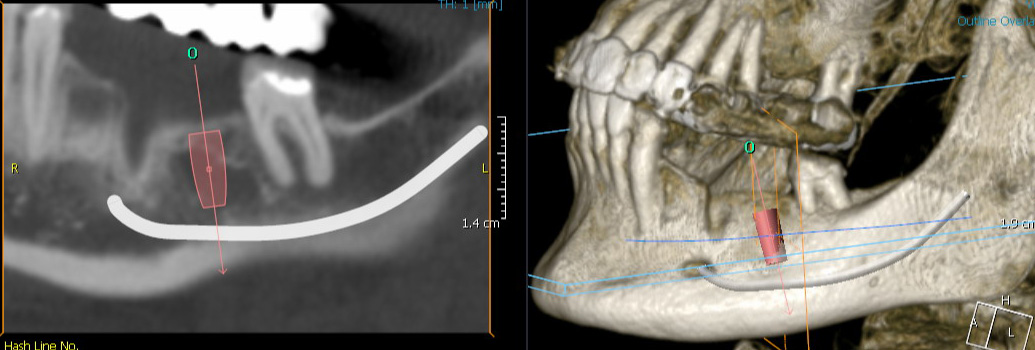

In der Mund-Kiefer-Gesicht-Chirurgie, insbesondere in der Implantologie, ist eine exakte, bildgebende Diagnostik unerlässlich. Erstklassige und umfassende Diagnosen sind die Grundlage, um Planung und Behandlung so präzise wie möglich zu gestalten. Nur auf Basis detaillierter Diagnostik ist ein chirurgischer Eingriff am Gesicht oder den knöchernen Strukturen des Kopfes sicher planbar. Nerven und andere sensible anatomische Strukturen liegen dicht beieinander. Vor einer Behandlung müssen möglichst alle eventuellen Risiken erkannt werden.

Unseren Patienten, den überweisenden Kollegen und uns bieten neueste diagnostische Verfahren Praxis eine sichere Therapie und ein überzeugendes Ergebnis. Wenn die klassische Diagnostik keine eindeutigen Ergebnisse liefert oder wenn Fragen zur Knochenstruktur, Knochenqualität und zu anatomischen Gegebenheiten offen bleiben, kann eine detailliertere, 3-dimensionale Diagnostik erfolgen.